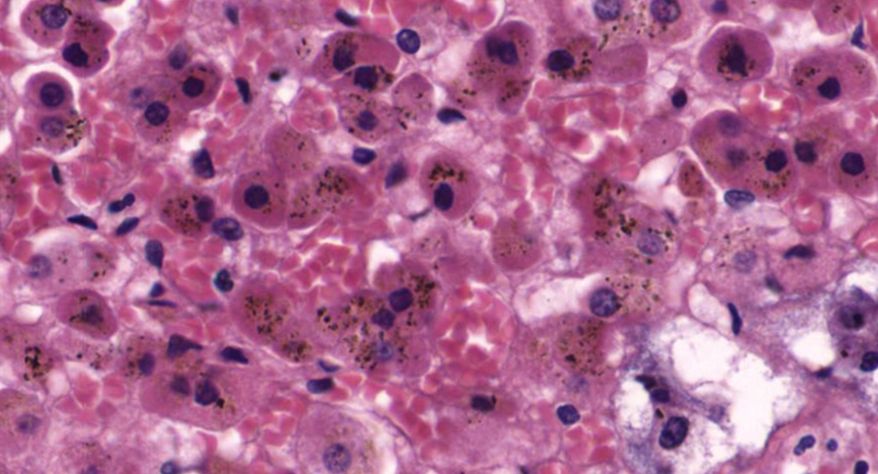

低倍镜:分出皮质及髓质。皮质由表至里分为三个带:高倍镜:(1)皮质:①球状带的细胞聚集成球状团块,细胞较小,矮柱状或多边形,核小,着色深,胞质弱嗜碱性,有少量脂滴。②束状带很厚,细胞排列成束状,在细胞之间有少量结缔组织及丰富的血窦,高倍镜观察束状带的细胞体积较大,呈多边形,核大而着色浅,胞质有许多脂滴,在制片过程中被溶解,因此胞质染色很淡。③网状带细胞排列成索,细胞索互相吻合成网,索间有丰富的血窦,胞质染色略呈嗜酸性,脂滴很少,核小着色浅。(2)髓质:髓质和皮质交界参差不齐,髓质细胞较大,呈多边形,此外还有少量交感神经节细胞,后者胞体较大,胞质着色浅,常单个或2~3个成群散布于髓质内。

1.全景图

2.被膜

3.皮质

4.球状带(10x)

5.球状带(40x)

6.束状带(10x)

7束状带(40x)

8.网状带(10x)

9.网状带(40x)

10.网状带细胞内脂褐素

11.髓质

12.嗜铬细胞

13.交感神经节细胞

14.中央静脉